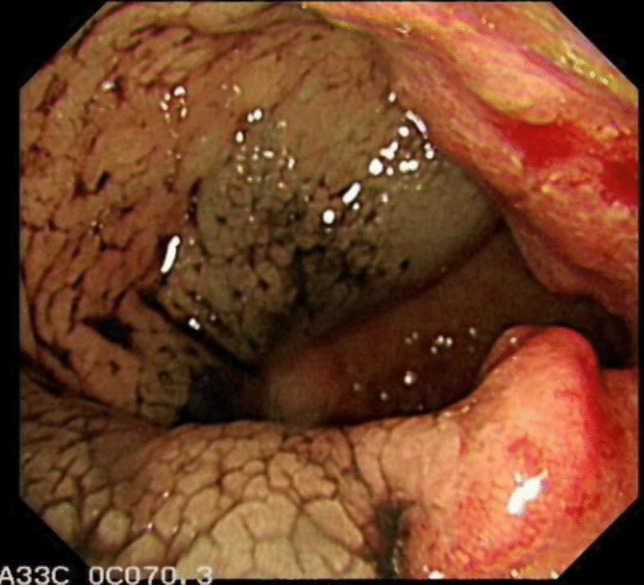

Methods: This study retrospectively analyzed clinical data from 109 patients who underwent neoadjuvant therapy and laparoscopic radical resection for rectal cancer at Weifang People's Hospital from January 2020 to December 2022. Of these, 43 patients received an endoscopic submucosal injection of nano-carbon suspension (experimental group), with 22 patients receiving the injection before neoadjuvant therapy and 21 patients receiving it 24 h before surgery. The remaining 66 patients did not receive the nano-carbon injection (control group). All patients received neoadjuvant therapy according to guidelines and were operated on by the same surgical team. By comparing the number of detected lymph nodes and short-term clinical outcomes among the three groups, the study aimed to investigate the impact of the endoscopic submucosal injection of nano-carbon and the timing of injection on the surgical quality for patients with rectal cancer undergoing neoadjuvant therapy.